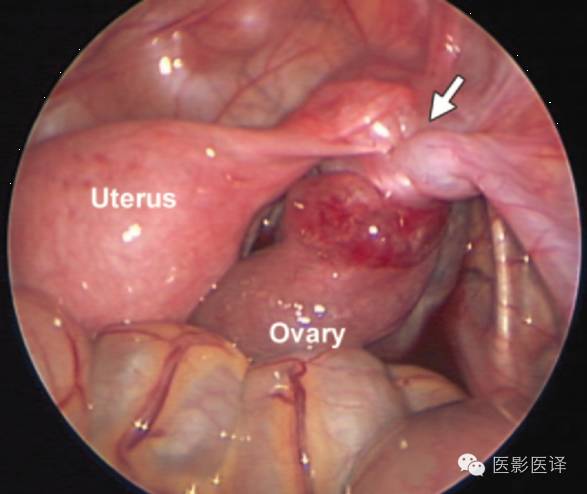

生后囊肿抽吸术可以减少扭转的几率,且争议较少,因为胎儿出生后诊断更加明确,手术并发症风险更小,因此生后囊肿抽吸术的“价值和安全性是明确的”。新生儿卵巢囊肿达4-5cm或是更大者,应该考虑卵巢抽吸术。生后卵巢囊肿最保守的治疗是视察一段时间,因为卵巢囊肿可能会自发缩小。生后新生儿应该每4-6周进行一次超声检查,直到卵巢囊肿消失、增大、出现症状或持续6个月无变化。手术指征通常包括复杂性、有症状、持续增大及超过6个月的囊肿。Zampieri等发现大于5cm的囊肿通常需要手术治疗。新生儿卵巢囊肿进行腹腔镜术后是可行且安全的。针对巨大卵巢囊肿,为了保存卵巢功能,应该行保守手术治疗,如囊肿剥除术或开窗术。如果视察期间发生卵巢扭转,可以尝试卵巢扭转矫正法来保存卵巢功能(图21)。如果扭转可能导致败血症或血流动力学不稳定,应该考虑行卵巢切除术和输卵管-卵巢切除术。